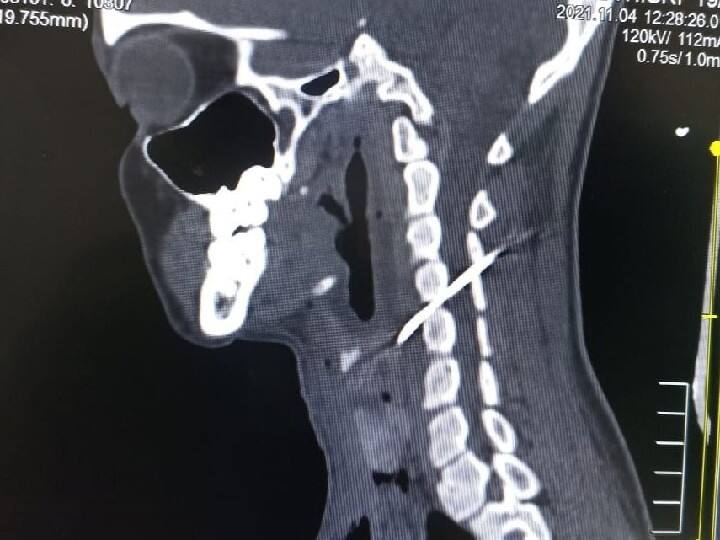

கோவை, தியாகராய நகர் பகுதியைச் சேர்ந்த 19 வயது இளம்பெண் ஒருவர், கழுத்தை அறுத்து கொண்டு தற்கொலைக்கு முயன்றுள்ளார். இதை அடுத்து கழுத்து அறுபட்ட நிலையில் கடந்த 2ஆம் தேதி கோவை அரசு மருத்துவ கல்லூரி மருத்துவமனையில் சிகிச்சைக்காக அனுமதிக்கப்பட்டார். அவரை பரிசோதித்த மருத்துவர்கள் கழுத்தில் வெளிப்புற காயங்கள் இருந்ததால் முதலுதவி செய்தனர். எனினும் கழுத்தில் ஏற்பட்ட காயம் குணமான பின்னரும், அவருக்கு கழுத்து வலி இருந்துள்ளது. இதனை அடுத்து அப்பெண்ணிற்கு சிடி ஸ்கேன் பரிசோதனை செய்த போது, 7.5 செ.மீ. அளவுக்கு நீளமான தையல் ஊசி, கழுத்தில் மூச்சு குழாயில் இருந்து கழுத்து தண்டு பகுதியில் மூளைக்கு செல்லும் ரத்தக்குழாய் அருகில் இருப்பது தெரியவந்தது. இது குறித்து மருத்துவர்கள் அவரிடம் கேட்ட போது, தற்கொலை செய்து கொள்ள தான் அந்த ஊசியை கழுத்தில் குத்தியதாக தெரிவித்துள்ளார்.

இதனை அடுத்து மூளைக்கு செல்லும் ரத்த குழாய்க்கு அருகே தையல் ஊசி இருப்பதால் அறுவை சிகிச்சை செய்து ஊசியை எடுப்பது என்பது சவாலாகவும், நோயாளியின் உயிருக்கு ஆபத்து ஏற்பட வாய்ப்பு இருந்தது. தண்டு வட மருத்துவர்கள், ரத்த நாள மருத்துவர்கள், காது, மூக்கு, தொண்டை மருத்துவர்கள், மயக்கவியல் மருத்துவர்கள் கலந்து ஆலோசித்து அறுவை சிகிச்சை செய்ய முடிவெடுத்தனர். இதன்படி கழுத்தில் இருந்து தண்டுவட எலும்பு பகுதியில் அறுவை சிகிச்சை செய்து மூச்சுக் குழாயில் இருந்து தண்டுவடத்தின் வழியாக கழுத்தின் பின்புறம் சென்று கொண்டிருந்த ஊசி கண்டறியப்பட்டது. பின்னர் நவீன சி.ஆர்.எம் எக்ஸ்ரே கருவியின் மூலம் ஊசி இருக்குமிடம் உறுதி செய்யப்பட்டு, அந்த ஊசி மெதுவாக துல்லியமாக வெளியே எடுக்கப்பட்டது.